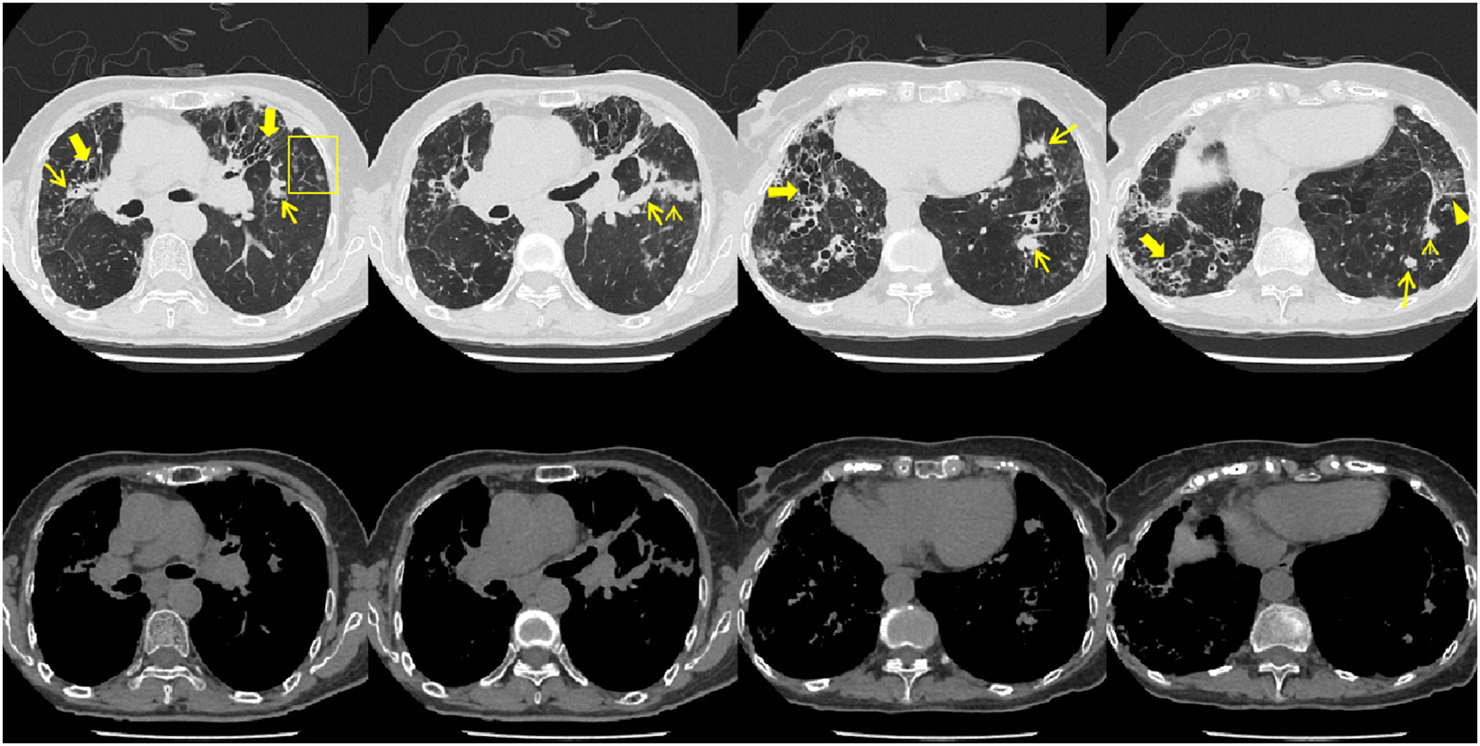

In July 2023, the patient visited the local hospital for “chest pain, cough, and sputum”, and the results of chest CT showed multiple bronchiectasis with mucus plugs in both lungs (Figure 1), but no antifungal treatment was administered. The patient was readmitted to our hospital on 18 September 2023, with exacerbated symptoms of chest tightness and wheezing. Laboratory results showed white blood cell count (10.32 × 109/L) and the absolute eosinophil count (3.84 × 109/L) (Table 1), the Bronchoalveolar Lavage Fluid (BALF) culture was positive for Aspergillus fumigatus, and the sputum culture was positive for Candida albicans. The peripheral blood Glactomannan test (GM) was negative. A transbronchial lung biopsy suggested acute and chronic inflammation of the bronchial mucosa, with mucus plug formation, was diagnosed with acute exacerbation of chronic obstructive pulmonary disease, with bronchodilation and concurrent infection. Itraconazole capsule was prescribed for oral treatment (200 mg qd for 1 year). During outpatient treatment phase, the patient experienced recurrent symptoms accompanied by intermittent febrile episodes.

FIGURE 1

Patient’s chest CT imaging on 14 Sep 2023. The chest computed tomography showed bronchiectasis (bold arrows), mucus pluggings (narrow arrows) and chronic pleuropulmonary fibrosis (triangles) before treatment, which were typical manifestations of ABPA. Bronchopneumonia (arrow heads) and tree-in-bud opacities (yellow boxes) were found, indicating cocurrent IPA.